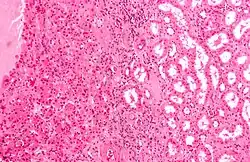

An oncocyte is an epithelial cell characterized by an excessive number of mitochondria, resulting in an abundant acidophilic, granular cytoplasm. Oncocytes can be benign or malignant.

- Hürthle cell (thyroid gland only)

- Oxyphilic cell

- Askanazy cell

- Apocrine-type metaplasia (breast gland only).

- Oncocytic cell